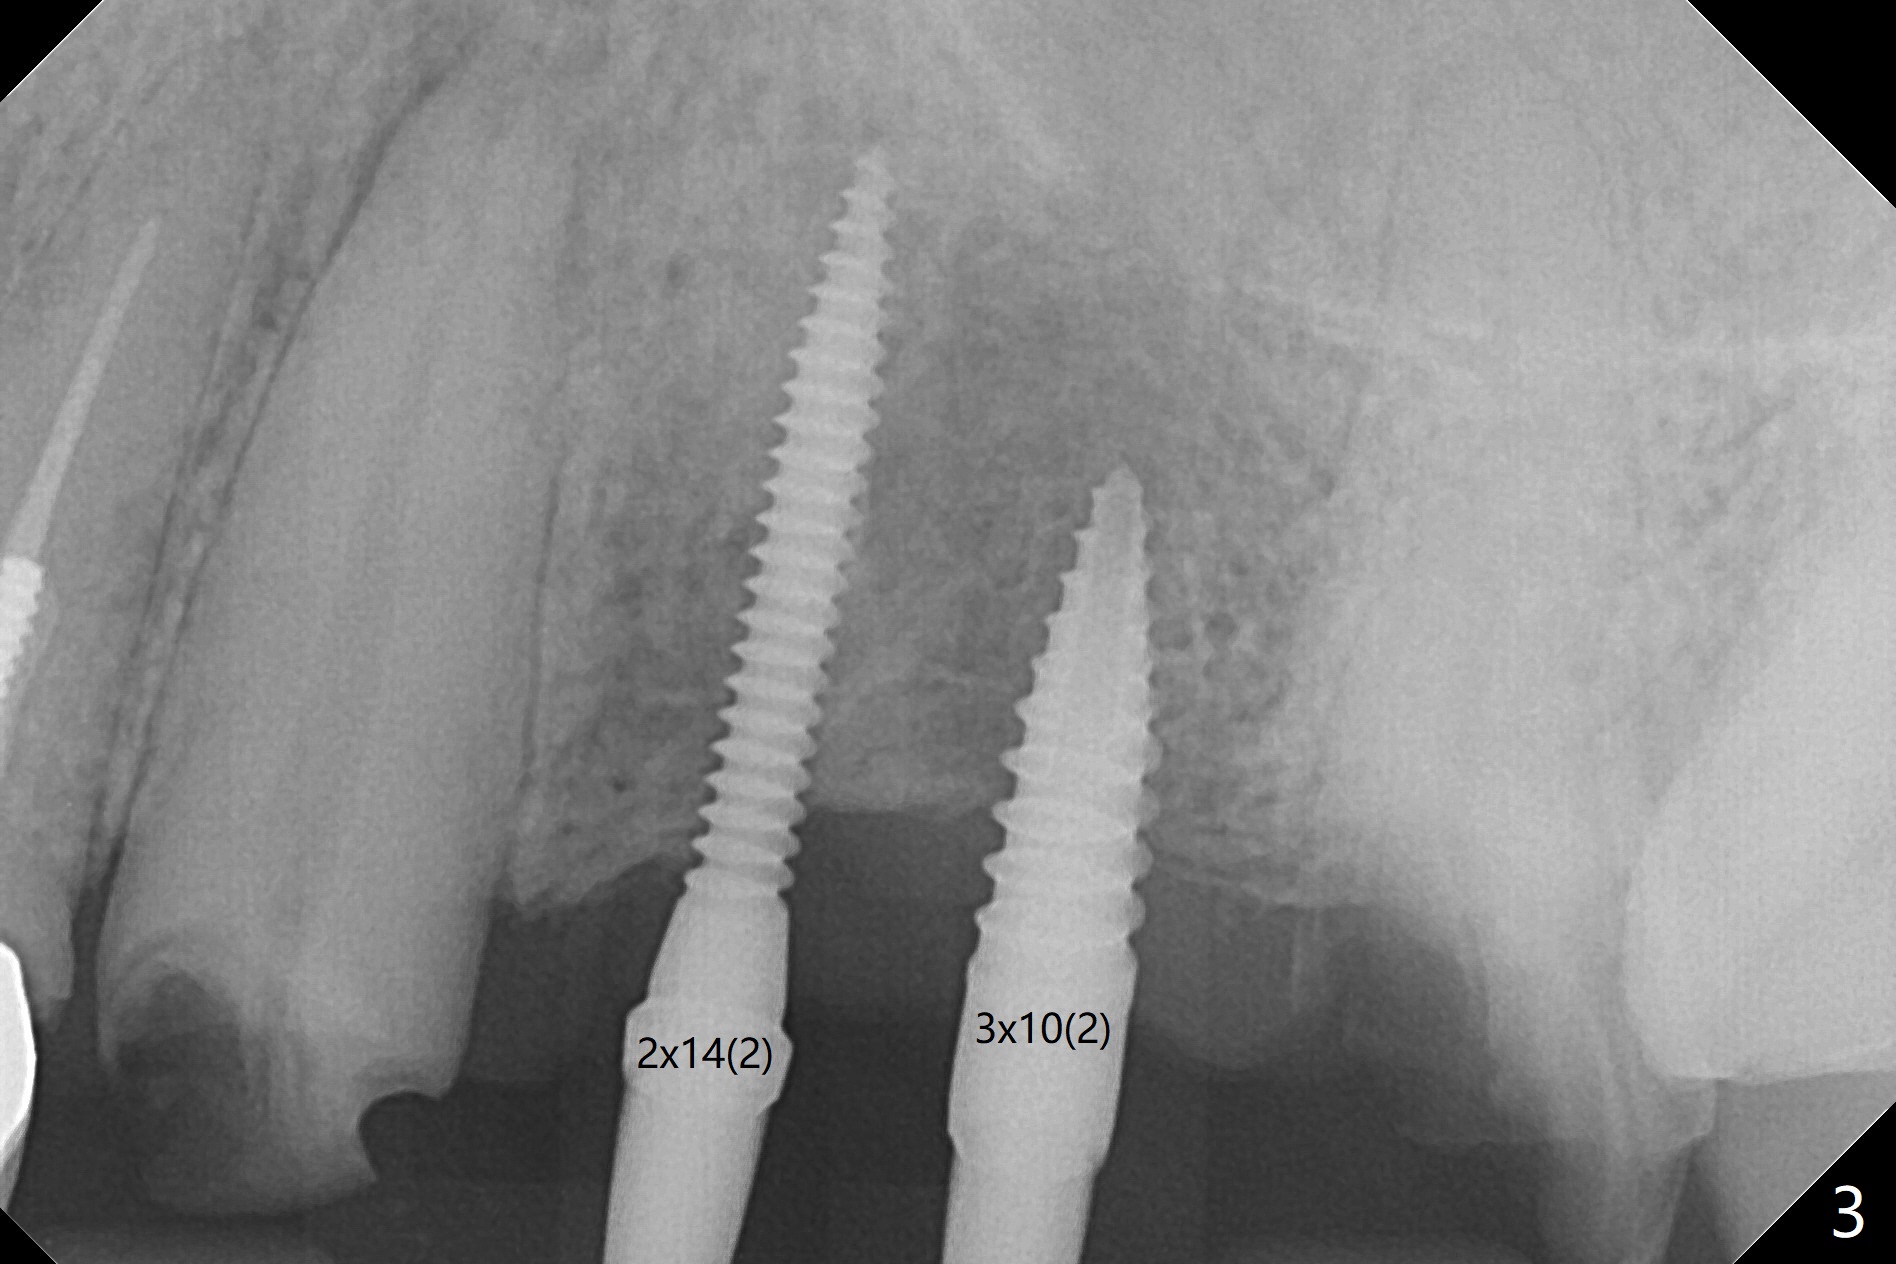

The edentulous ridge is narrow between the residual roots of #11 and 14 (Fig.1). Since the bone density is low in the edentulous area, DIO bone expanders are used (e.g., #1 (1/1.6 mm) Fig.2) after 1.2 mm initial drill. A 2x14(2) mm 1-piece implant is placed at #12 with 4 mm ridge width, while a 3x10 (2) mm dummy implant is partially placed after use of Bone Expander #2 (1.3/2.3 mm). The latter is replaced by a definitive one (3x12(2) mm), while the one at #12 is placed deeper (Fig.4). After extraction and placement of PRF and Vanilla Graft for sinus lift (Fig.4 black *), a 5x10 mm 2-piece implant is placed at #14, while a dummy implant is placed at #11 (Fig.4,5). As the osteotomy at #11 is 4.9 mm longer than the dummy (Fig.5), a definitive one is 3 mm longer (Fig.6). Osteogen plug is placed in the apical portion of each socket at #11 and 14, while Vanilla and Osteogen are packed in the coronal portion of the socket (Fig.4,6 *). Although primary stability of each implant is not high (30/40 Ncm), splinted provisional with occlusal clearance seems to be sufficient for implant osteointegration. There is no discomfort 9 days postop (Fig.7). Impression is taken 3 months postop, since he plans to return to home country for business (Fig.8). Single unit crowns are cemented 4 months postop (Fig.9,10). The abutment screw at #14 needs retightening 6 months post cementation. The access hole slightly buccal. Chewing pain at #12 is reduced after occlusal adjustment 6.5 months post cementation (Fig.11).